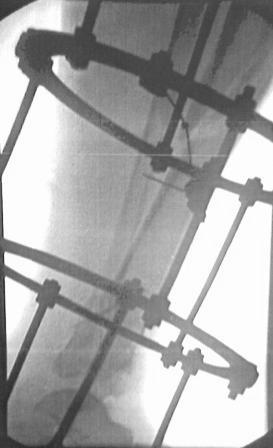

Больной 41г переведен из ЦРБ, травма в результате ДТП- 5 дней назад, произведена ПХО раны, наложена гипсовая повязка.

Об-но; начиная с с/з голени продольно - почти циркулярная рана, с признаками инфицирования - покраснение, отечность, усиление боли, местная т-ра и мутные кровянистые выделения из раны, и выраженная деформация голени. В отд нашей коллегой в экстренном порядке в задней поверхности голени щвы распушены, выпушено около 50мл мутной гематомы, АВФ, умеренная дистракция, антибиотики, и т.д.

Наш план; после устранения воспалительных процессов, перемонтаж аппарата, репозиция оставшихся смещений спицами с упорной плошадкой и стабилизация аппарата, дальше по обстановке.

2.Не могу, потому что аппарат Илизарова наложен нашей молодой коллегой в экстренном порядке, и несовсем удачно и с ошибками, но главную функцию для данного случая -дистракцию выполняет,( поэтому я писал, что будем делать перемонтаж.)